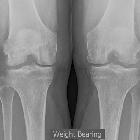

subchondraler Osteophyt

Central osteophytes, also known as subchondral or button osteophytes, are located within the joint and are thought to arise from endochondral ossification of a cartilaginous lesion .